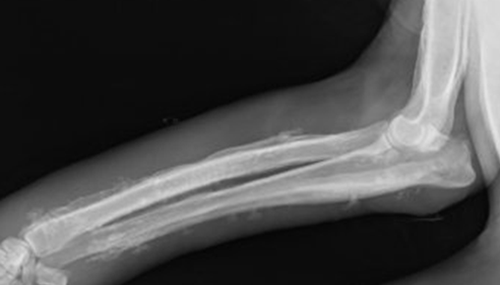

检查:厚皮性骨膜病的X线检查可见胫骨、腓骨、桡骨、尺骨等部位有增生性骨膜炎、弥漫性骨膜增厚。

诊断:根据皮肤及骨骼X线检查见增生性骨膜炎、弥漫性骨膜增厚的典型临床改变可作出诊断。